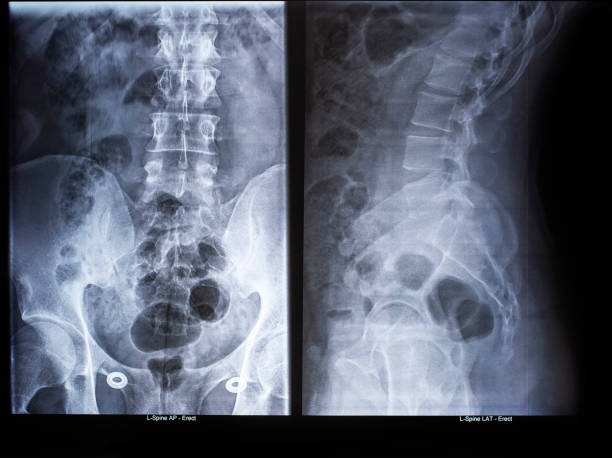

골반은 복부 하단에 위치하고 있는데 양쪽의 2개 볼기뼈와 후단부의 천골(엉치뼈)와 미골(꼬리뼈)로 구성되어 있으며 척추 부분과 하지를 연결하여 체중을 지탱하며 각종 내장과 자궁, 난소, 방광 등 주요 장기를 외부 충격에서 보호할 수 있습니다.

처장관절은 천골(엉치뼈), 장골(엉덩이뼈)가 만나는 부위로 외부 충격 혹은 골반이 힘을 주며 불편한 자세로 일어나거나 한쪽으로 체중이 쏠리는 잘못된 자세로 인하여 천장관절 주변으로 조직이나 인대 등에서 통증을 유발하는데 심할 경우 계단 오르내리는 것 자체도 어려워 질 수 있습니다.